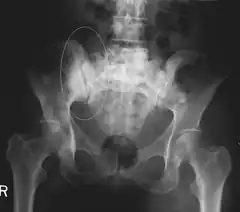

Sclerotic breast cancer metastases in the pelvis.

CT scan in the coronal plane of bone metastases of the hip bone, in a 60-year-old woman with parotid gland cancer. The more affected side is very irregular and sclerotic (visible as brighter in this presentation).